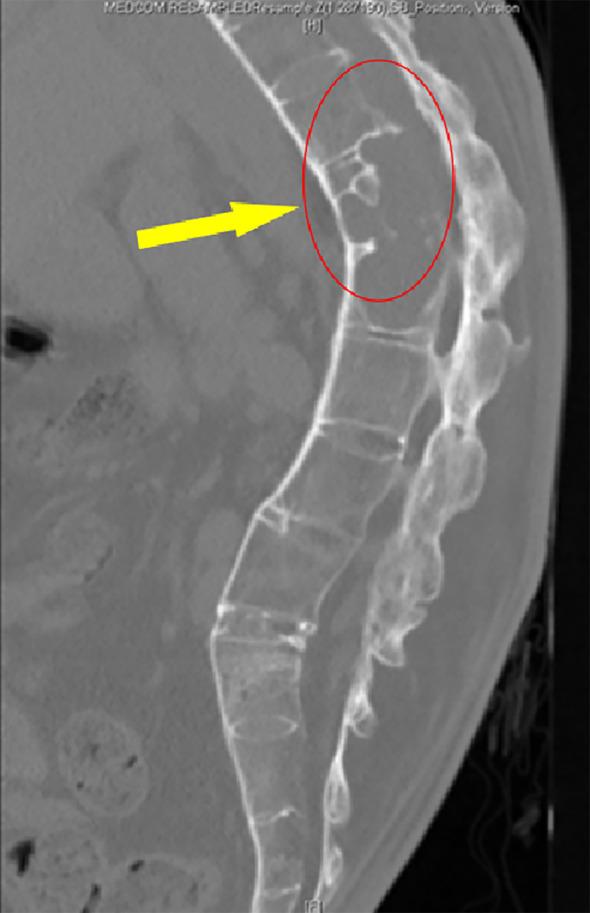

A 49-year-old male reported a 30-year history of thoracolumbar pain and limited mobility and was diagnosed with AS with dual complications of AL and ICSH. Before correction surgery, physical examination, x-ray, CT, MRI and Blood HLA-B27 examination were performed and a series of radiological parameters, including the degree of kyphosis and the T1-pelvic angle (TPA), were measured. Several days after surgery (Distal PSO was used), we performed examinations to check the patient's physical condition which showed the patient recovered remarkably. CTA was done, indicating that the patient's aorta moved anteriorly with the osteotomy side undamaged. A series of morphological parameters were measured again, including TPA, LL, and TK. CT and MRI were performed again, reflecting significant bone-to-bone fusion and successful recovery. The patient relieved the symptoms and regained his daily activities.

一名49岁男性有30年胸腰段疼痛及活动受限病史,被诊断为AS并伴有AL和ICSH双重并发症。在矫正手术前,进行了体格检查、X线、CT、MRI及血液HLA - B27检查,并测量了一系列放射学参数,包括后凸畸形程度和T1 - 骨盆角(TPA)。手术后几天(采用远端腰大肌松解术),我们进行检查以评估患者身体状况,结果显示患者恢复显著。进行了CT血管造影(CTA),表明患者的主动脉向前移动,截骨侧未受损。再次测量了一系列形态学参数,包括TPA、腰椎前凸(LL)和胸椎后凸(TK)。再次进行CT和MRI检查,显示有明显的骨对骨融合且恢复成功。患者症状缓解,恢复了日常活动。